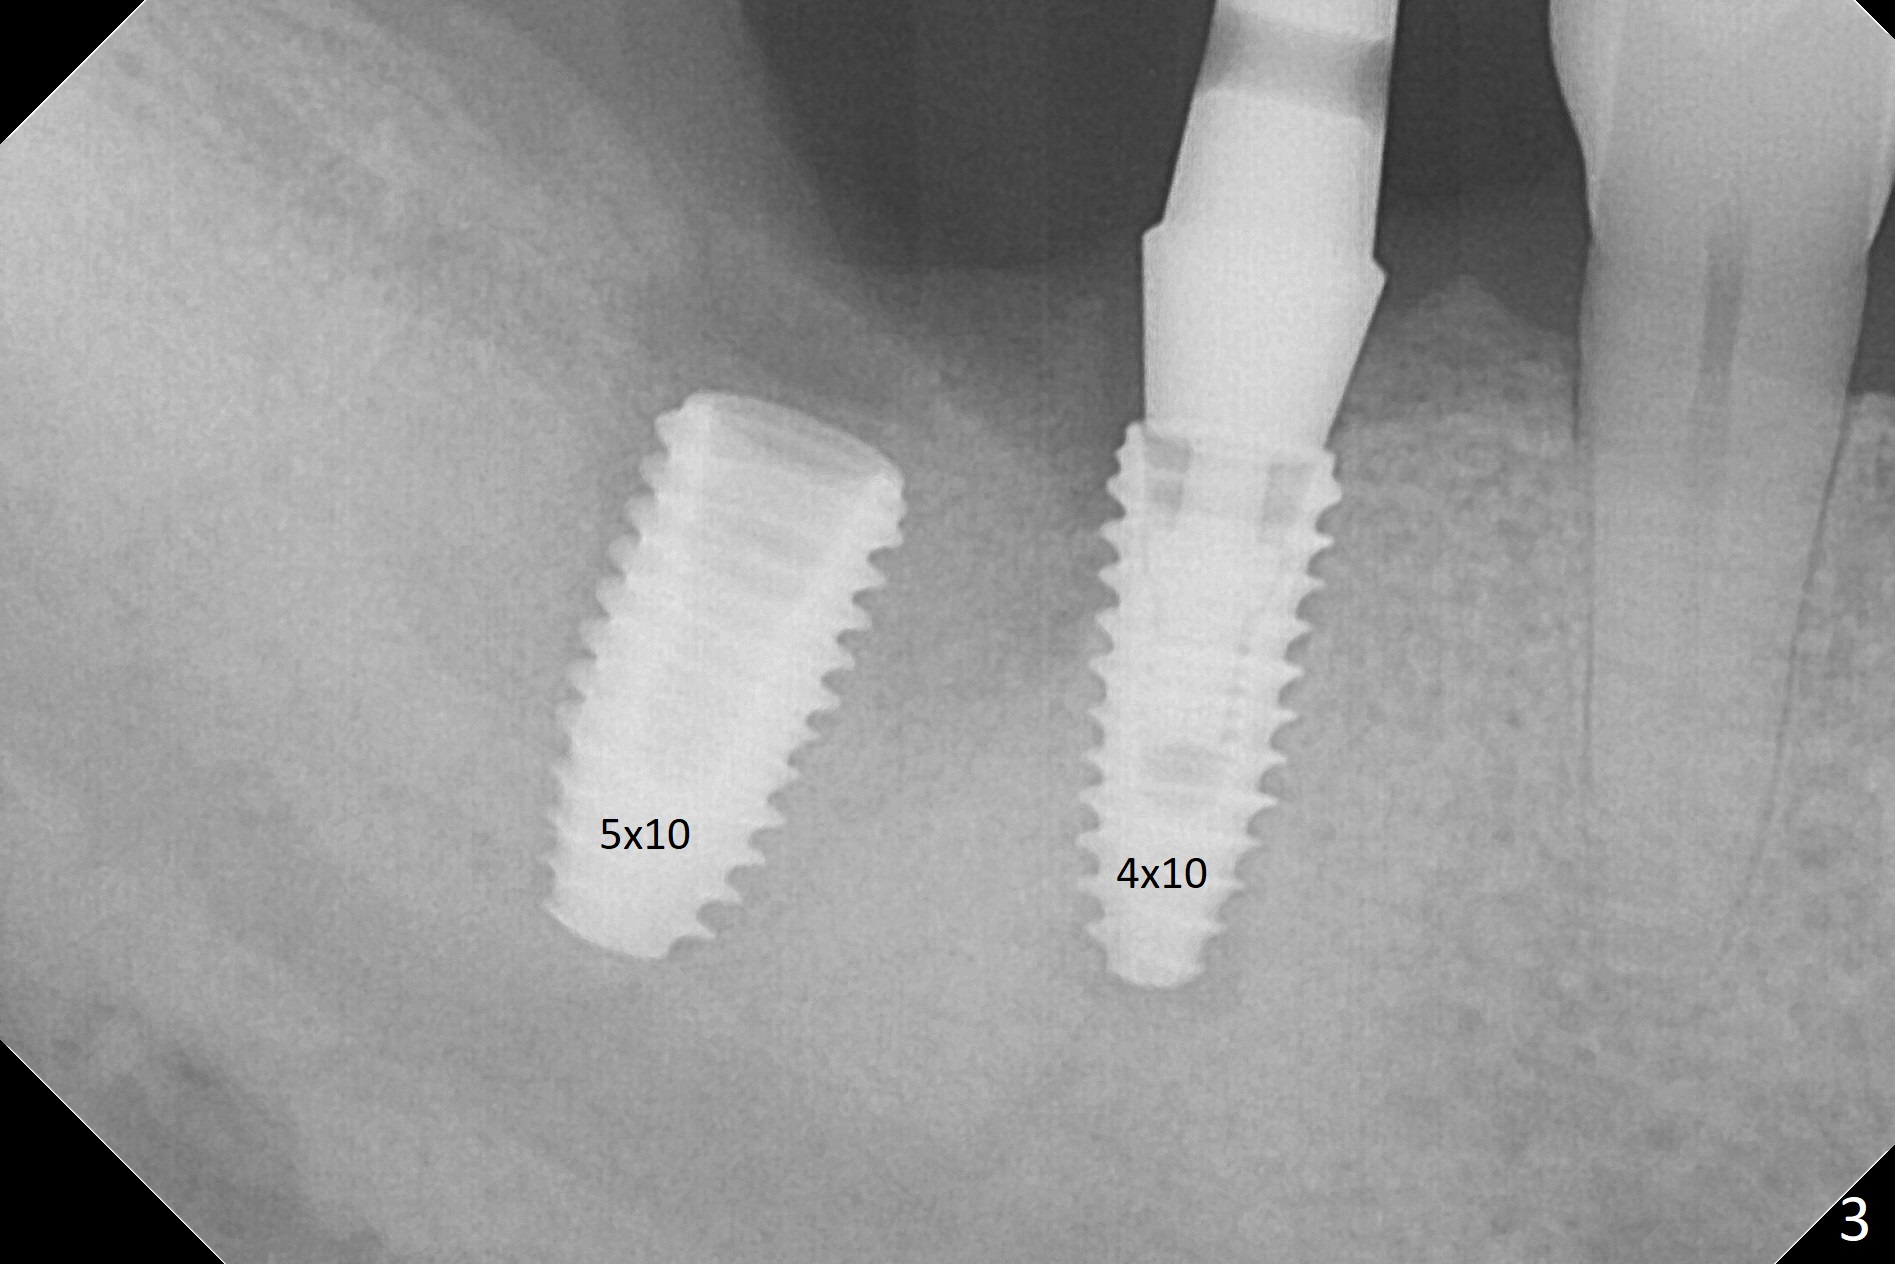

Osteotomy at the sites of #30 and 31 is initiated with Magic Split, followed by Magic Expanders (3.0 and 3.8 mm) at #31.  Initial depth of osteotomy is 13 mm with 2.2 mm drill (Fig.1).  After adjustment of the trajectory at #31 (Fig.1 arrow) and deepening the osteotomy by 2 mm, dummy implants are placed with stability (Fig.2).  Following increase in osteotomy at #31, the larger implant in fact loses stability (Fig.3).  The loose implant is pushed distal (Fig.4 arrow) with placement of autogenous bone mesial (*).  The stable implant at #30 (Fig.3) and its abutment (Fig.4) are used as a post to hold periodontal dressing, which covers the wound at #31 after placement of collagen plug and suturing.  In fact the same technique could be used when socket preservation was performed if an implant were placed at #30 at the same time.  When the periodontal dressing dislodges, the wound at #31 heals uneventfully (Fig.5,6).  The bone graft seems to remain in place 3 months postop (Fig.7).  The implant is uncovered with placement of a 6.8x7 mm healing abutment 4 months postop.  When a cementation abutment is placed and prepped, the buccal margin is much lower than the lingual (Fig.8 taken prior to cementation).  The patient enjoys mastication with the new implant crowns 3.5 months post cementation (Fig.9).